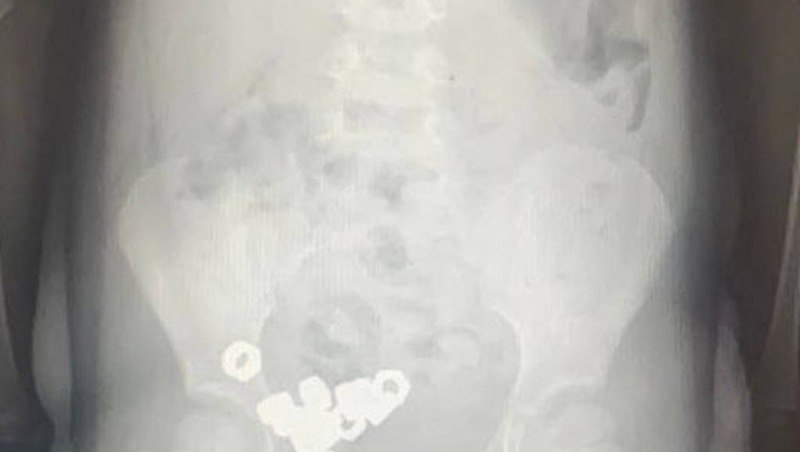

В Воронеже трехлетний мальчик проглотил стальных 16 гаек

Трёхлетнего мальчика доставили в приёмное отделение городской детской больницы №2 Воронежа после того, как родители заподозрили, что он мог случайно проглотить посторонние предметы.Горком36 - городской портал | Новости Воронежа

Ребёнок был госпитализирован для постоянного мониторинга состояния ввиду потенциальной угрозы возникновения серьёзных последствий. Поскольку обнаруженные объекты не обладали магнитными свойствами и не представляли собой химически агрессивные вещества, специалисты приняли решение о проведении консервативного лечения.